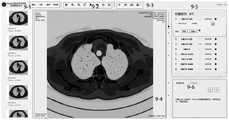

FIG. 9 is an interface for operating the CT information and reporting module according to an embodiment of the present invention;

FIG. 9 is a CT labeling interface for each patient with lung cancer. Each button in the frame 9-1 is used for adjusting the window width and the window level; the buttons in box 9-2 are used for image flipping, zooming in, zooming out, buffering, nodule display, CT information display, and immersion mode, respectively. Box 9-3 is used to click display of relevant results for the model, annotation, and review. A frame 9-4 displays the CT scanning result, and a rectangular frame in the CT scanning result identifies the positions of the nodules for the model and is endowed with numbers; the right sliding bar is used for sliding and switching the slices, and the identification is annotated to the slice pages with the nodules; the left side of the system is a preview of all cases of the patient, and the system can jump to a CT interface of the corresponding case by clicking one preview. The box 9-5 is used for sequencing and displaying the related information of each nodule, clicking one item of the information, expanding and displaying the related volume, the diameter of the nodule, the related characterization and other information below the item, and displaying the required characterization for selection by clicking a plus sign button on the characterization as shown in fig. 10; the box 9-6 is a report writing and exporting unit, and by clicking a certain item of the box 9-5, the text box seen by the image can automatically generate text information corresponding to the item; if the item is double-clicked, generating text information corresponding to all the nodules, clicking a copy button, and supporting the copying of the text; clicking the zoom button generates a pdf style report of all nodule information, as shown in fig. 11, supporting export of pdf documents.